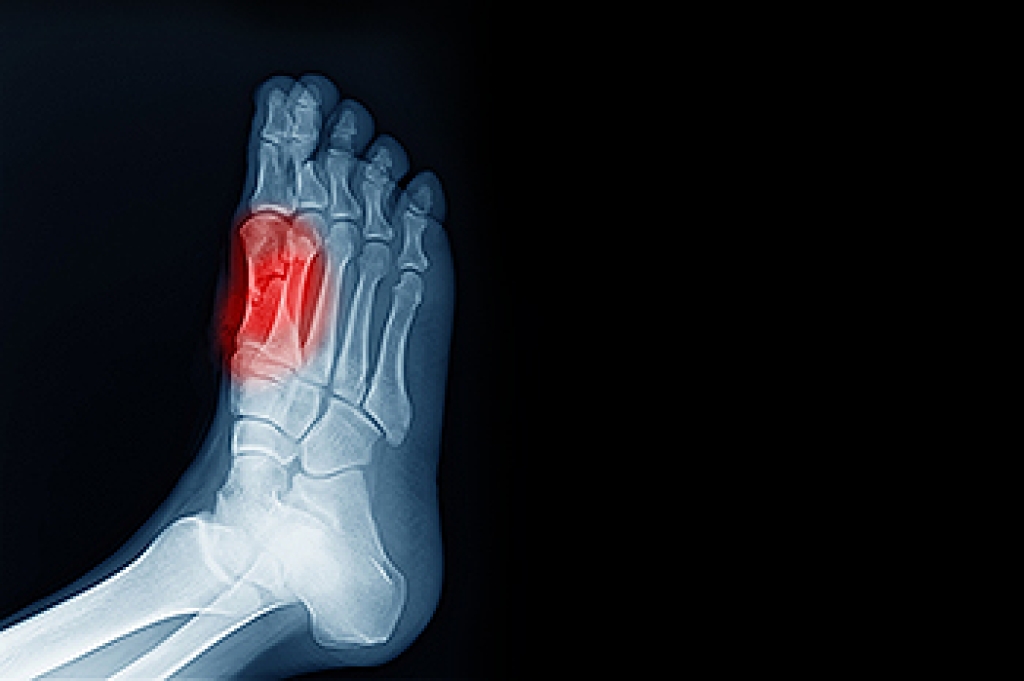

Sesamoiditis is the inflammation of the small sesamoid bones located beneath the big toe joint that help bear weight and support movement. This condition often develops in athletes, dancers, or anyone placing repeated stress on the ball of the foot. Risk factors include high-impact activities, wearing improper footwear, and foot structure abnormalities. Pain is typically felt under the big toe, especially when walking, running, or bending the toe. Symptoms may include swelling, tenderness, and difficulty pushing off the foot. A podiatrist can provide customized treatment such as rest strategies, orthotics, and targeted exercises. If you have pain in this part of your foot, it is suggested you schedule an appointment with a podiatrist who can accurately diagnose and treat what may be going on.

Sesamoiditis is a condition of the foot that affects the ball of the foot. It is more common in younger people than it is in older people. It can also occur with people who have begun a new exercise program, since their bodies are adjusting to the new physical regimen. Pain may also be caused by the inflammation of tendons surrounding the bones. It is important to seek treatment in its early stages because if you ignore the pain, this condition can lead to more serious problems such as severe irritation and bone fractures.